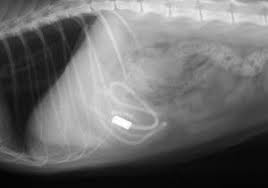

Enlarged Kidney X Ray. Hydronephrosis can occur in one or both kidneys. Because kidney enlargement often causes no symptoms it is often discovered incidentally on an imaging study such as an an abdominal ultrasound x ray or ct scan.

Normal kidney size in adults. Generally kidney enlargement is a symptom of an underlying disease or disorder of the kidneys. My dog was diagnosed with enlarged kidneys after and x ray and ultrasound.

Treatment of an enlarged kidney will often involve recognizing and treating the underlying condition. The normal reference range sizes for kidneys are 2 5 3 5 x the length of l2 for dogs and 2 3 x the length of l2 for cats. The kidneys the ureters the bladder and urethra. Hydronephrosis can occur in one or both kidneys.